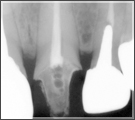

根管治療とは、リーマーやファイルと呼ばれる器具で細菌に感染してしまった歯質や神経を徹底的に除去し、歯の根の病気(根尖病変)を治療・予防するものです。

根っこの中は直接見ることができず、形も人それぞれなので完全に細菌を取り除くことが非常に難しく、しかも細菌を取り残した状態で詰め物を詰めたり、クラウ ン(差し歯・かぶせ物)をかぶせてしまうと、後々細菌が増殖してトラブルが出てきてしまうこともあるからです。

レントゲン撮影と虫歯のチェックをします。   こちらが通常肉眼では見えにくい部分で設備が無い医院では大まかな治療で終える場合があります。   しっかりと根元を治療することにより虫歯の菌を除去することができます。